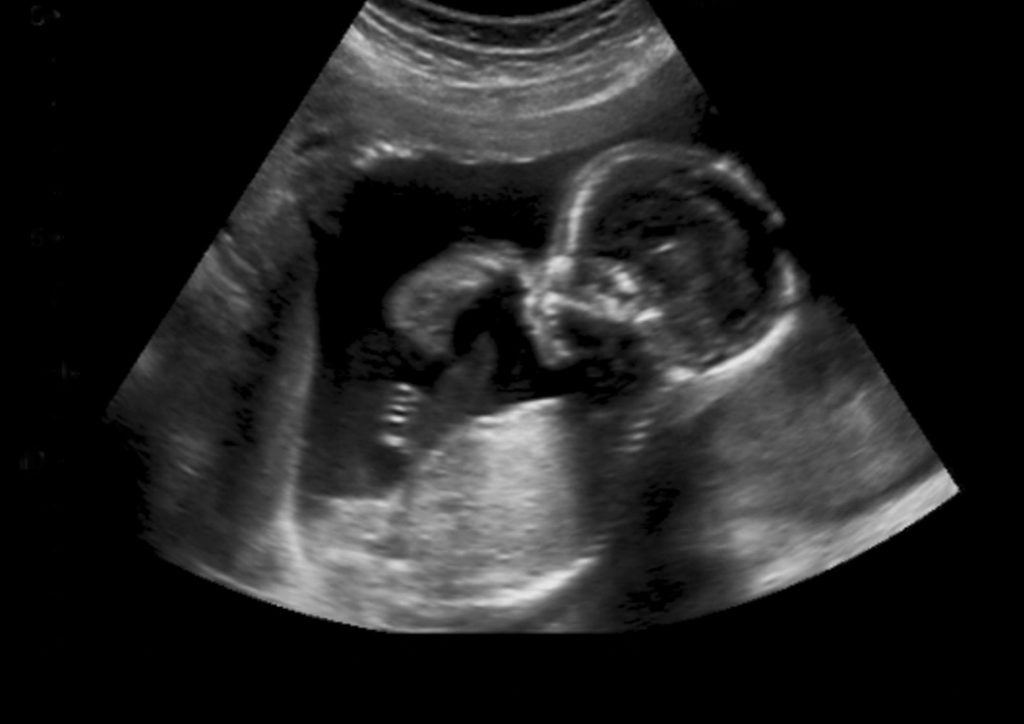

Baby risks, explained clinically

A structured, reference-based overview of major risks from conception through the newborn period—what increases risk, what reduces risk, how problems are detected, and what treatments/outcomes commonly look like.

ScopeConception → pregnancy (by trimester) → delivery/transition → neonatal/NICU → key congenital conditions → feeding.